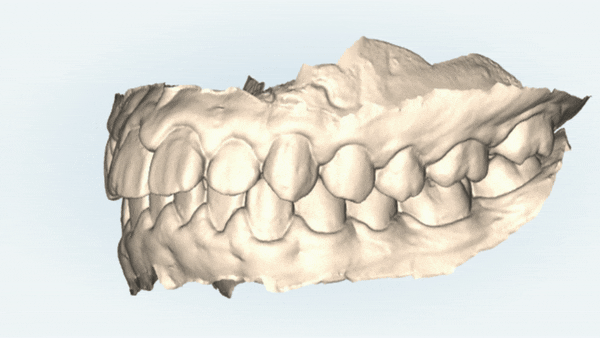

돌출된 앞니를 개선하기 위해서

상대적으로 중요도가 떨어지는

소구치를 발치하고

앞니들이 들어갈 공간을 마련해주어야 하는데요,

그 공간을 이용하여

앞니들을 뒤로 당겨주어야 합니다

악궁이 좁아 삐뚤빼뚤했던 치아들이

교정 후

발치된 공간으로 치아들이 올바르게 배열되며

교정치료가 만족스럽게 잘 마무리 되었습니다.